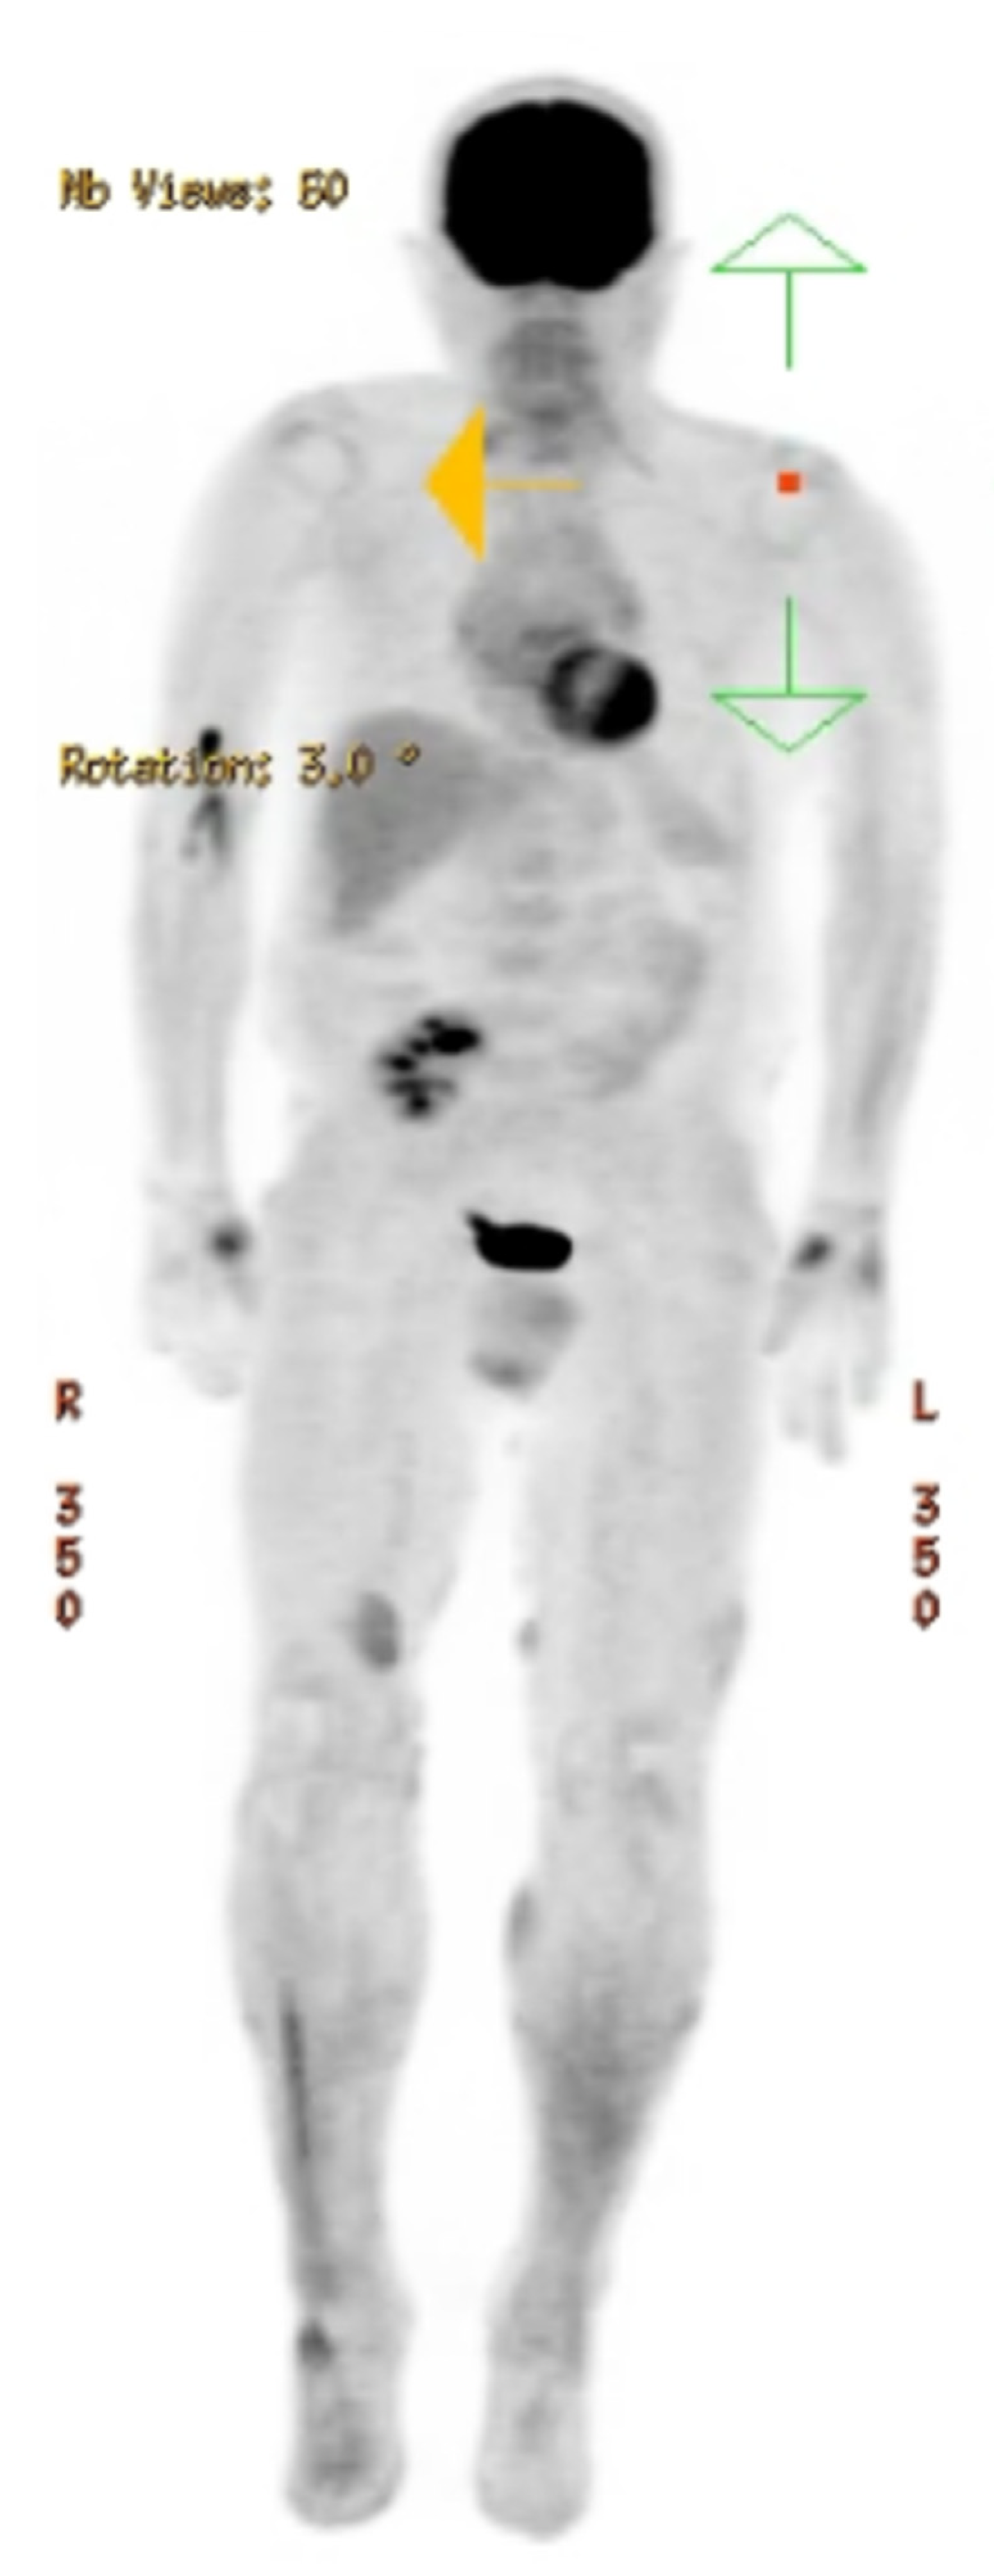

2. Case Report